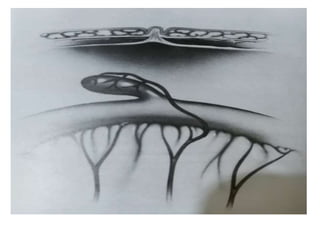

distended loops of intestine.

Barium Contrast Enema= Classic findings are based on

the presence of an abrupt narrow transition zone b/w the

normal dilated proximal colon and a smaller-caliber

obstructed aganglionic segment.

Rectosigmoid Index= Measurement of diameter of the

rectum to that of sigmoid colon during contrast enema.

Rectal diameter that is same or smaller than the sigmoid

colon suggests Hirschsprung disease.